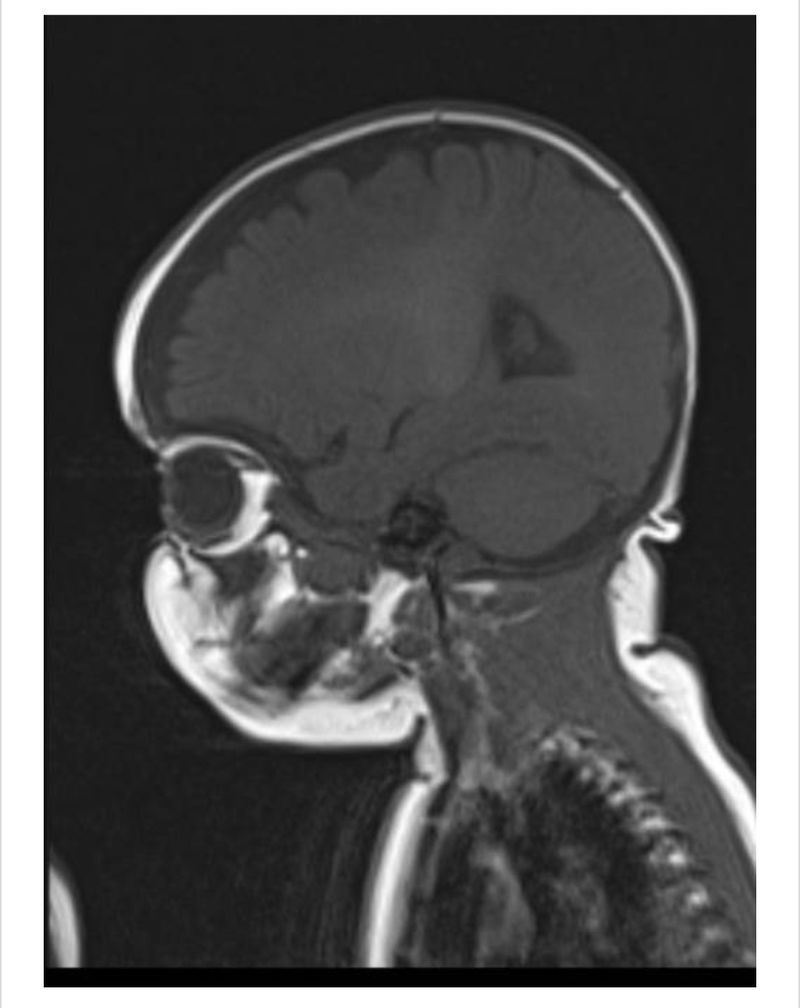

Ik kan me hier nog sterk houden. Met tranen in mijn ogen weliswaar, maar het lukt nog. Op de beelden is niet één, maar twee tumoren in het hoofdje van Mace te zien. Alleen dat woord “tumor”, valt al heel zwaar. Het is dus geen cyste, maar een echte tumor. Een kleintje aan zijn oogzenuw en een grotere centraal aan de hersenstam. De volgende stap is om een biopsie te nemen om daaruit op te maken of we over iets goedaardigs praten of echt een agressieve kanker. Weer onwetendheid. De biopsie zou snel kunnen plaatsvinden, afhankelijk wanneer de beste kinderneurochirurgen en anesthesisten hier kunnen zijn. Op de uitslag van de biopsie zullen we een week moeten wachten.

De kanker zit op een ongunstige plek

Eerst spraken ze over “een veilige” weg voor de biopsie. Wij dachten toen dat ze een buisje via neus of keel bedoelden, maar nee, ze bedoelden hiermee dat ze een kleine incisie maken in het hoofd en geen gezond weefsel doorsnijden. De artsen gaan dus al effectief in mijn kleine perfecte mensje snijden. Wat er dan volgt weten we niet. Misschien een operatie, chemo of bestraling, dit is allemaal afhankelijk van wélk soort tumor er zit. De plaats van de tumoren is ongunstig. De kinderarts laat het aan de neurochirurgen over, maar kaart wel al aan ze het waarschijnlijk niet helemaal kunnen weghalen, omdat de hersenstam ontzettend gevoelig en gevaarlijk is.